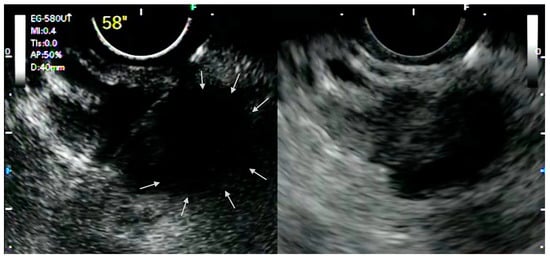

The ability of CH-EUS to depict the macro- and micro-vascularization of solid lesions in a real-time manner allows the detection of avascular areas, which represent fibrotic or necrotic areas that harbor poor diagnostic potential and that should be avoided during tissue acquisition. Indeed, it has been demonstrated that EUS-FNA has lower sensitivity for pancreatic adenocarcinoma with avascular areas on CH-EUS [9]. In this perspective, it was postulated that CH-EUS could be used to guide EUS-FNA ( Figure 1 ).

In 2017, Minaga et al. reported a case of EUS-guided drainage of an infected WOPN under CH-EUS guidance. There is an inability to depict the target lesion and its margins in B-mode due to heterogeneous echogenicity; thus, a CH-EUS was performed to enhance the contrast between the targeted WOPN and the surrounding tissues, enabling the assessment of the microvasculature and hemodynamics of the collection in real time and the ability to safely puncture it and perform the EUS-guided drainage [29].